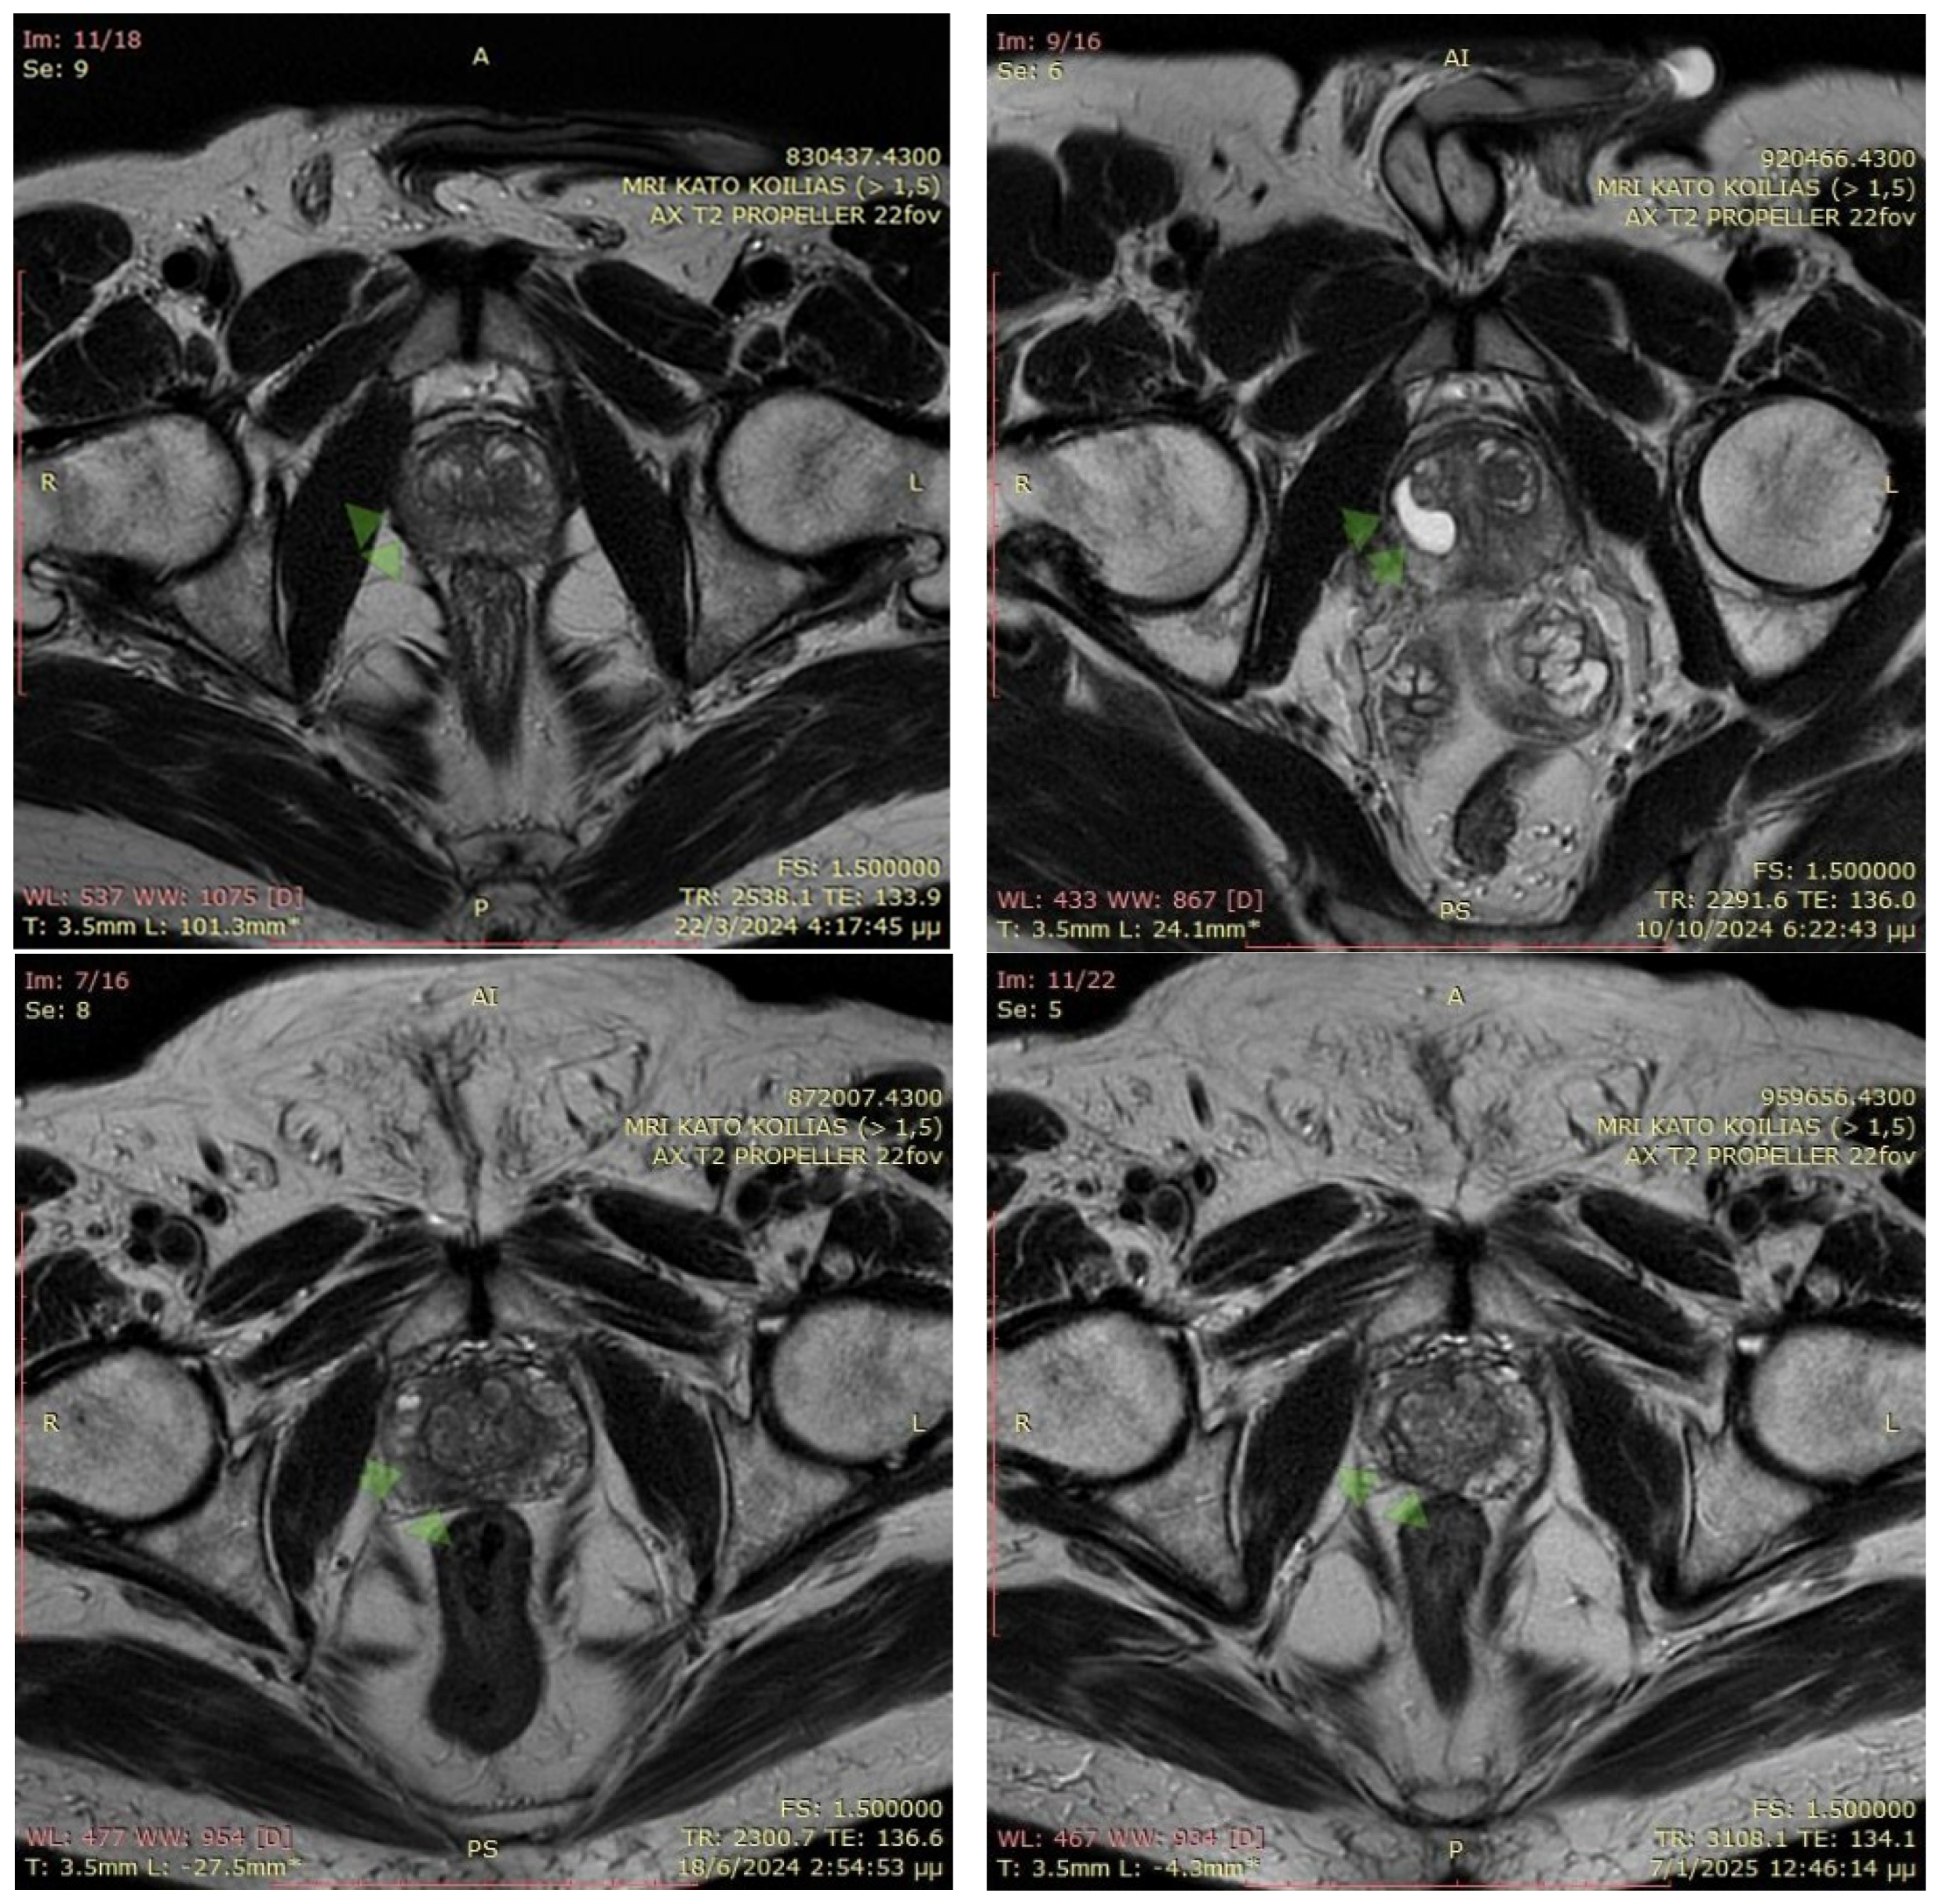

The MRI images illustrate axial T2-weighted scans of the prostate before and after EchoLaser focal therapy for prostate cancer with fiducial markers. In the pre-treatment MRI (22 March 2024 and 18 June 2024, respectively), the prostate appears relatively homogeneous, with a marked region of interest that may indicate a cancerous lesion. Fiducial markers were placed prior to the procedure to enhance precision in targeting the tumor. In the post-treatment MRI (10 October 2024 and 7 January 2025, respectively), significant structural alterations are visible within the prostate, including a well-defined hypointense area corresponding to necrotic tissue, a typical post-ablation finding. The presence of fiducial markers ensures accurate monitoring of treatment effects, confirming that the laser ablation successfully induced thermal damage to the targeted region while preserving surrounding healthy tissue (Figure 1).

Figure 1. MRI of two patients pre-biopsy and after the EchoLaser therapy with fiducial markers procedure. The arrows in the figure indicate the locations of the lesions.